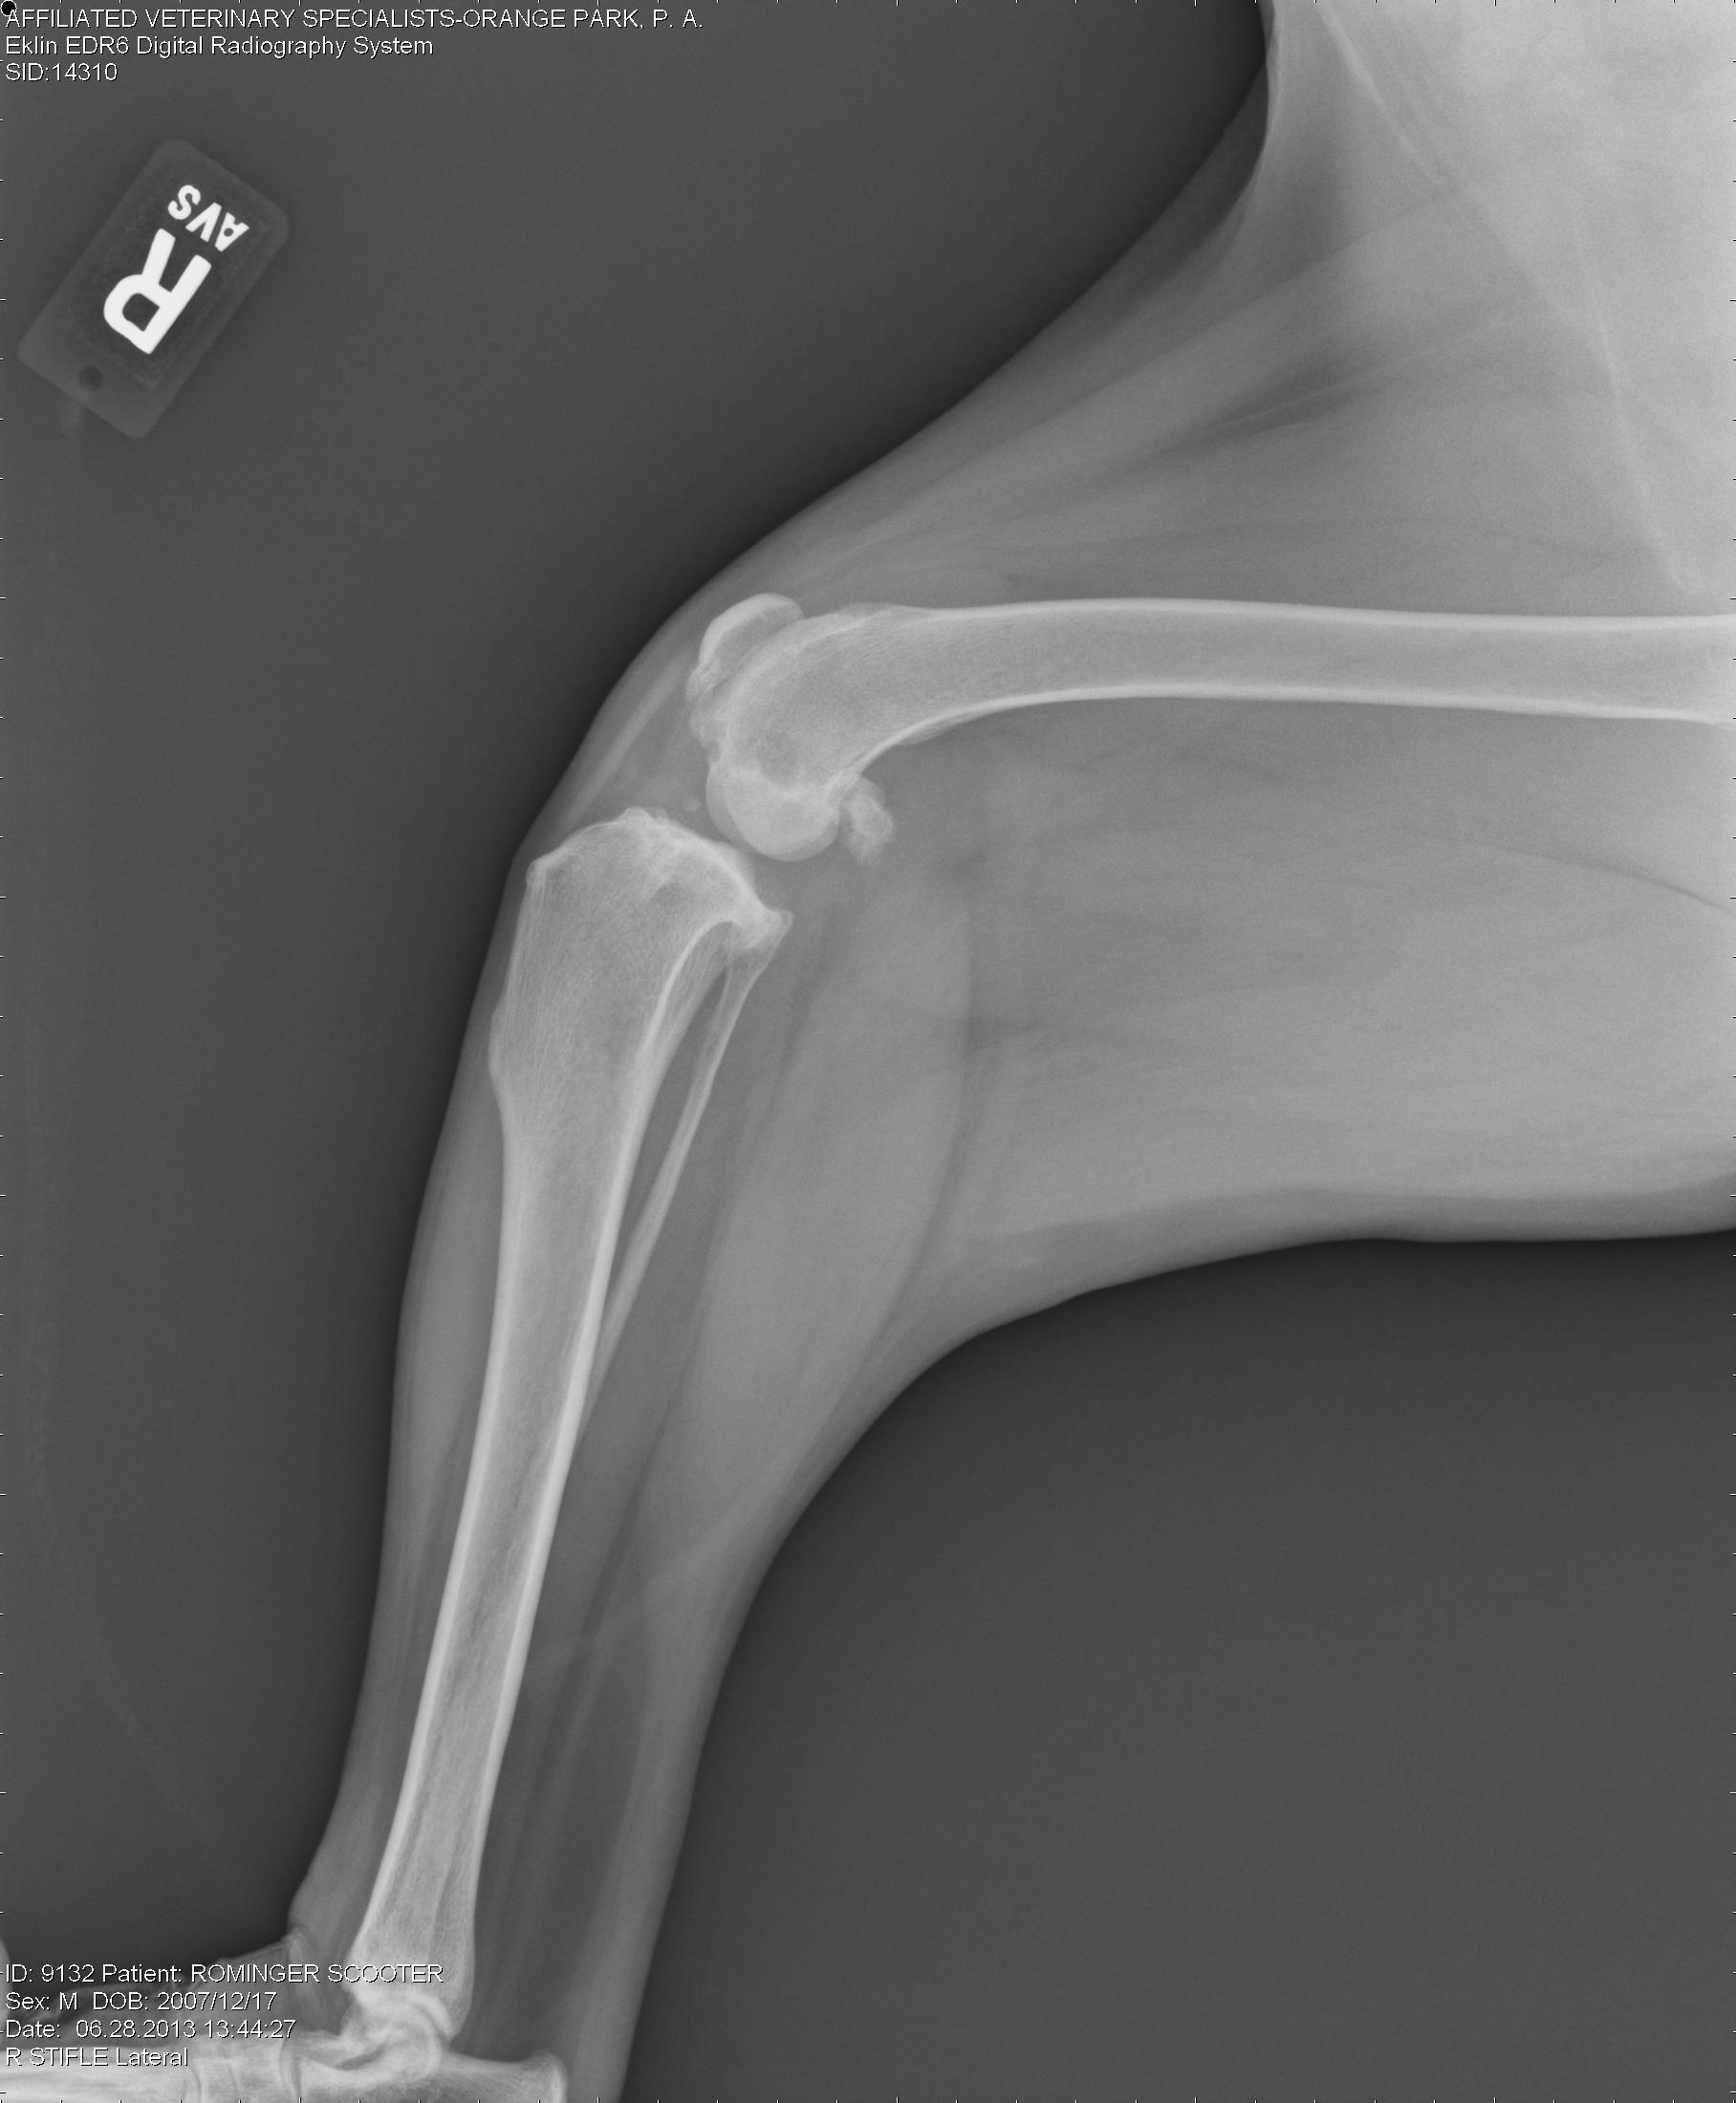

Right knee – note the joint swelling, arthritic changes, and forward movement of the tibia in relation to the femur.